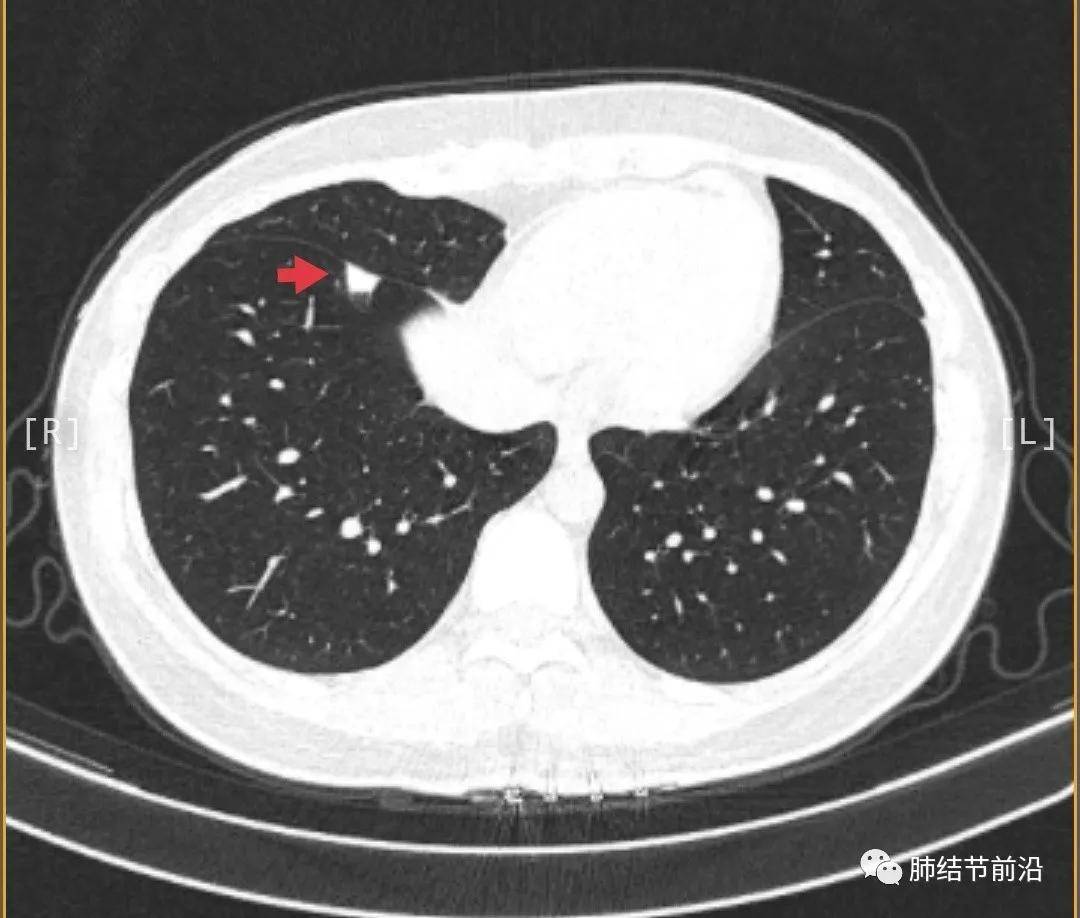

肺结节是指肺内直径小于或等于3cm的类圆形或不规则形病灶,影像学表现为密度增高的阴影,边界清晰或不清晰的病灶。